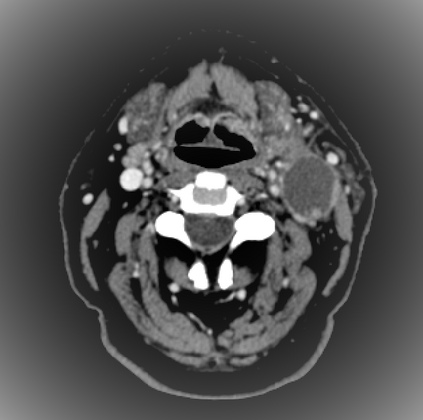

Organ at risk (OAR) segmentation is a critical process in radiotherapy treatment planning such as head and neck tumors. Nevertheless, in clinical practice, radiation oncologists predominantly perform OAR segmentations manually on CT scans. This manual process is highly time-consuming and expensive, limiting the number of patients who can receive timely radiotherapy. Additionally, CT scans offer lower soft-tissue contrast compared to MRI. Despite MRI providing superior soft-tissue visualization, its time-consuming nature makes it infeasible for real-time treatment planning. To address these challenges, we propose a method called SegReg, which utilizes Elastic Symmetric Normalization for registering MRI to perform OAR segmentation. SegReg outperforms the CT-only baseline by 16.78% in mDSC and 18.77% in mIoU, showing that it effectively combines the geometric accuracy of CT with the superior soft-tissue contrast of MRI, making accurate automated OAR segmentation for clinical practice become possible. See project website https://steve-zeyu-zhang.github.io/SegReg